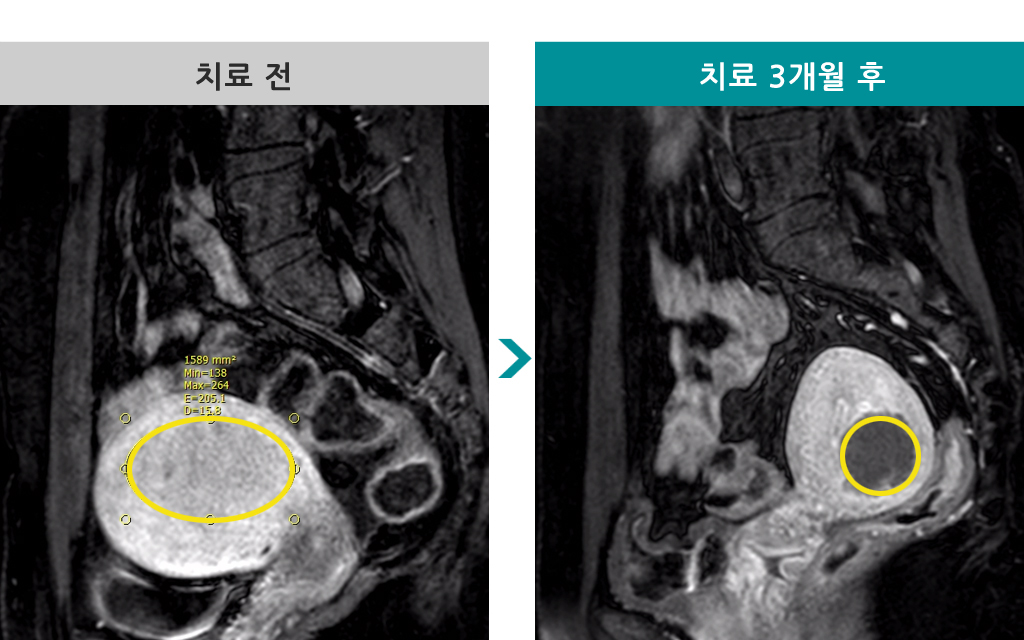

50세 [자궁선근증 색전술] 전후 MRI사진 비교